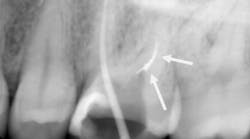

By 2:22 p.m., I was taking periapical x-rays with the gutta-percha to check my working lengths and evaluate the separated files. The x-ray showed that my access wasn’t as open as I originally thought it to be. The canal curved in two places, which caused the file separations. At this point I had two separated files—the 0.1 Twisted File (TF) file and the 15 mm hand file I had used to bypass the canal.